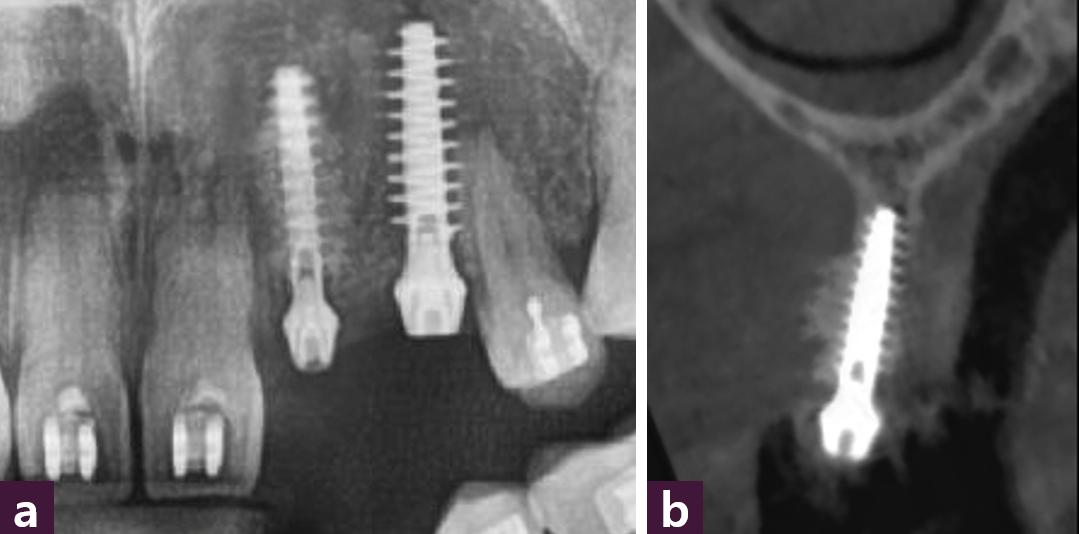

#22 부위의 CBCT소견으 로 치조정 부위에서는 약 4 mm 정도의 골폭을 보이고 있 으며, 중간부에서는 전치부의 concavity로 약 2.5 mm 정도 의 골폭을 보이고 있고 기저부 (apex)에서는 4 mm 이상의 골 폭이 있는 것을 확인할 수 있 다 [그림 12].

식립 직후 파노라마와 #22 임플란트의 CBCT 소견으로, concave 했던 순측면에 골 이식이 된 것을 볼 수 있다 [그림 17].